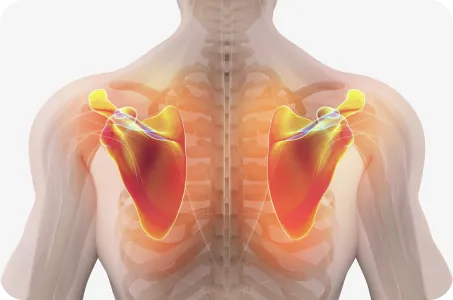

굽은 등의 경우, 견갑골의 위치가 척추에서 멀어져 있으며, 어깨 앞쪽의 근육은 긴장되어 있고 뒤쪽 근육은 늘어나 있습니다. 이 상태로 팔을 사용하게 되면 어깨의 건(힘줄)과 주변 인대가 늘어나거나 끊어지기 때문에 아픈 부위만 계속 치료한다면, 통증은 재발할 수 밖에 없습니다.

회전근개 파열, 어깨 충돌 증후군, 관절 와순 손상, 이두근건병증, 오십견, 석회화건염, 어깨 점액낭염 등 어깨 질환의 증상은 다양하지만, 결과적으로는 어깨 관절이 틀어진 상태에서 과도하게 사용한 것이 주요 원인입니다.

그래서 연산당당한방병원의 어깨 치료는 틀어진 관절을 바로잡는 것에서부터 출발합니다.